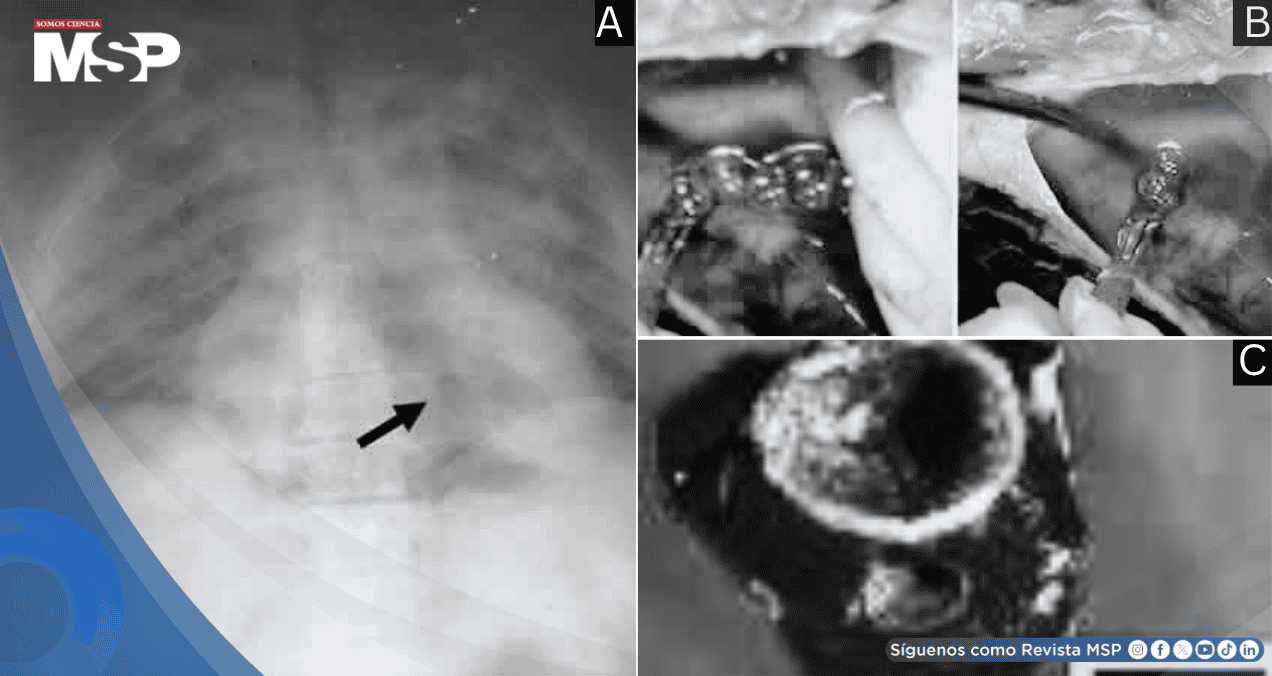

La radiografía previa a la autopsia mostró presencia masiva de gas en la circulación portal y en el ventrículo derecho.

Durante la disección cardíaca se documentó mediante video la emisión masiva de burbujas de gas al incidir la pared del ventrículo derecho, que se encontraba marcadamente distendido y flotaba anormalmente en el líquido pericárdico. El quiste hepático estaba vacío y presentaba signos evidentes de punción reciente.